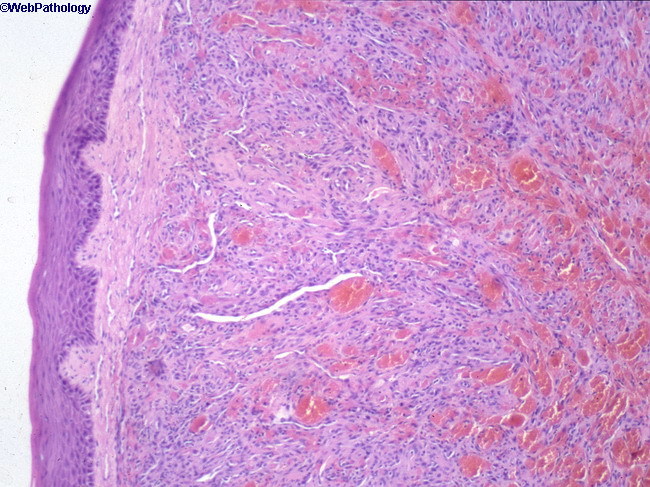

The promontory sign is seen in:

1 Tufted angioma

2 Glomeruloid hemangioma

3 Spindle cell hemangioendothelioma

4 Acroangiodermatitis of Mali

5 Kaposi’s sarcoma

Kaposi’s sarcoma

The promontory sign refers to the formation of new vessels around existing vessels and adnexal structures. This is seen in Kaposi’s.